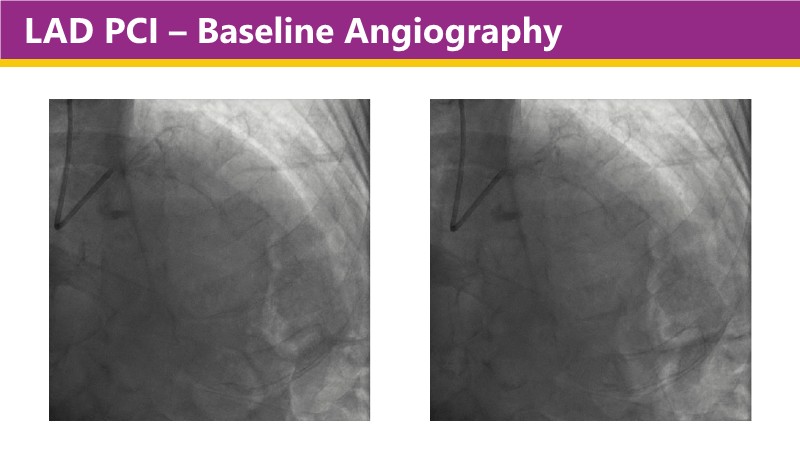

Learn how this technology works, review the supporting evidence, and follow step-by-step case examples demonstrating optimal stent expansion and an efficient calcium modification workflow in daily practice.